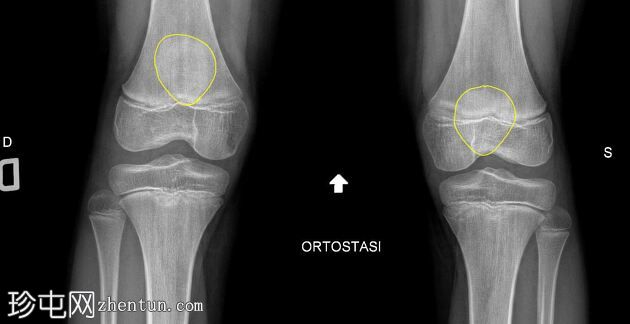

髌骨袖状骨折

一名篮球运动员在跳高后出现剧烈疼痛和功能丧失。

年龄:11岁

右膝

X线片

正位 -

负重位

髌骨下极可见一小块薄骨碎片,伴有髌骨高位,Insall-Salvati比值为1.5(V.N. 0.8 - 1.2)。膝前可见软组织肿胀。左膝正常。

儿童髌骨骨折并不常见。髌骨袖状骨折是一种仅见于儿童的特殊类型骨折,由肌肉快速收缩引起。髌骨高位是最明显的体征。这种骨折,即髌骨骨膜“袖套”脱离髌骨,会继续形成新的骨骼,逐渐增大直至与髌骨大小相当。治疗方法包括快速复位,通常还需要对撕裂的髌腱进行内固定。未经治疗的髌骨袖套骨折的并发症包括髌骨高位、膝前疼痛和股四头肌萎缩,导致活动严重受限。